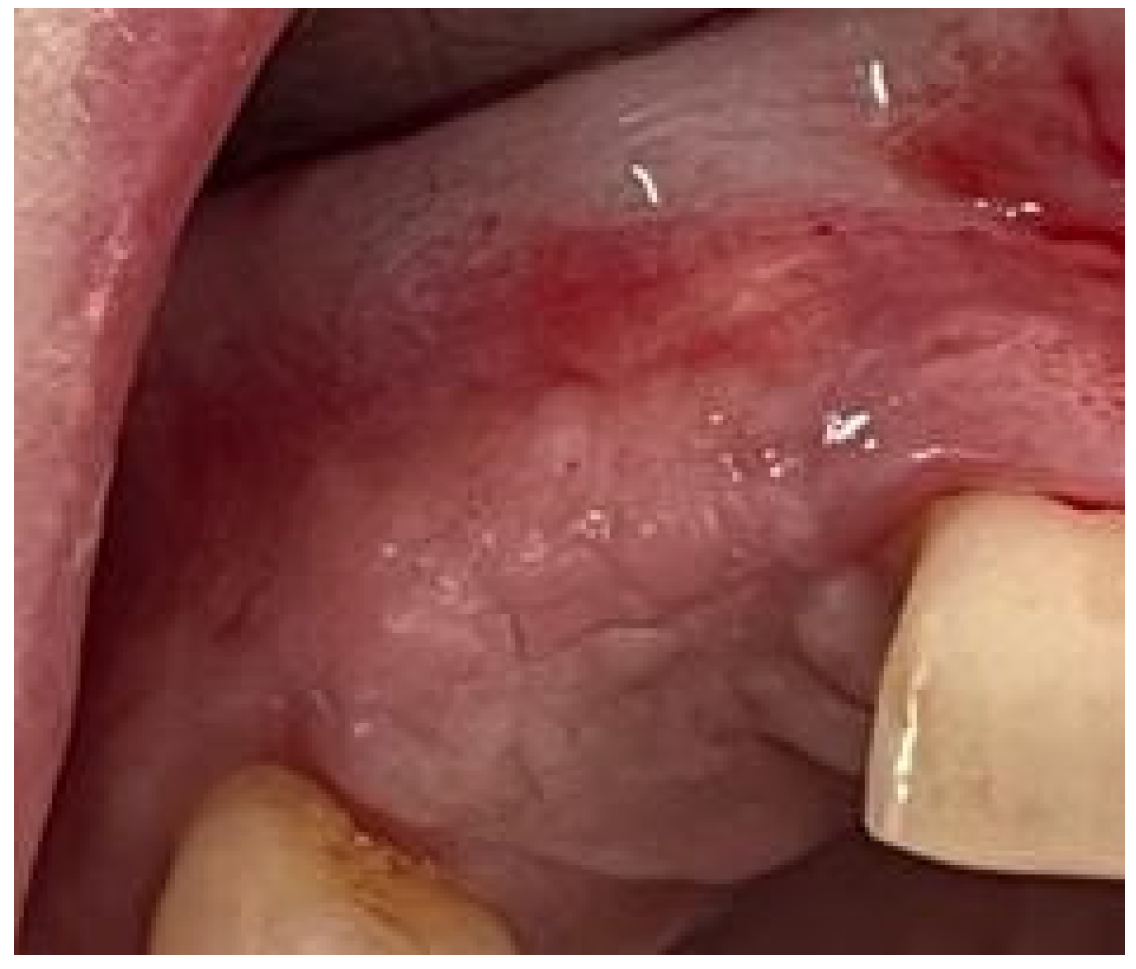

A 27-year-old woman presented to the dental clinic for aesthetic and masticatory dysfunction after a difficult odontectomy ten years ago. The provisional removable acrylic appliance (flipper) unsatisfied her and created a social disadvantage for the young woman. After a complete intraoral and extraoral examination (Figure 1A,B) and a cone-beam computerized tomography (CBCT) evaluation (Figure 2), the missing teeth 1.3, 1.2, and a complete palatal and buccal loss of bone with a marginal reconstructed alveolar bovine particles bone resulting from an earlier operation in the maxillary region were observed.

Figure 1. The initial intraoral aspect of the patient proposed a gingival graft before the bone augmentation: (A) the buccal view, (B) the occlusal view.